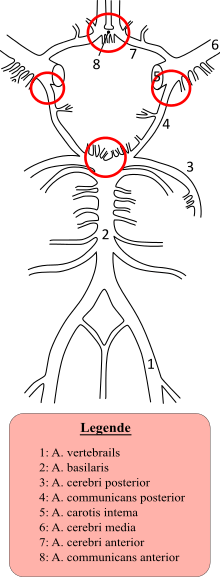

Most cases of SAH are due to trauma.[14] In 85 percent of cases of spontaneous SAH, the cause is rupture of a cerebral aneurysm—a weakness in the wall of one of the arteries in the brain that becomes enlarged. They tend to be located in the circle of Willis and its branches. While most cases of SAH are due to bleeding from small aneurysms, larger aneurysms (which are less common) are more likely to rupture.[1]

In 15–20 percent of cases of spontaneous SAH, no aneurysm is detected on the first angiogram.[15] About half of these are attributed to non-aneurysmal perimesencephalic hemorrhage, in which the blood is limited to the subarachnoid spaces around the midbrain (i.e. mesencephalon). In these, the origin of the blood is uncertain.[1] The remainder are due to other disorders affecting the blood vessels (such as arteriovenous malformations), disorders of the blood vessels in the spinal cord, and bleeding into various tumors.[1] Cocaine abuse and sickle cell anemia (usually in children) and, rarely, anticoagulant therapy, problems with blood clotting and pituitary apoplexy can also result in SAH.[7][15] Dissection of the vertebral artery, usually caused by trauma, can lead to subarachnoid hemorrhage if the dissection involves the part of the vessel inside the skull.[16]

If a cerebral aneurysm is identified on angiography, two measures are available to reduce the risk of further bleeding from the same aneurysm: clipping[38] and coiling.[39] Clipping requires a craniotomy (opening of the skull) to locate the aneurysm, followed by the placement of clips around the neck of the aneurysm. Coiling is performed through the large blood vessels (endovascularly): a catheter is inserted into the femoral artery in the groin and advanced through the aorta to the arteries (both carotid arteries and both vertebral arteries) that supply the brain. When the aneurysm has been located, platinum coils are deployed that cause a blood clot to form in the aneurysm, obliterating it. The decision as to which treatment is undertaken is typically made by a multidisciplinary team consisting of a neurosurgeon, neuroradiologist and often other health professionals.[1]

In general, the decision between clipping and coiling is made on the basis of the location of the aneurysm, its size and the condition of the patient. Aneurysms of the middle cerebral artery and its related vessels are hard to reach with angiography and tend to be amenable to clipping. Those of the basilar artery and posterior cerebral artery are hard to reach surgically and are more accessible for endovascular management.[40] These approaches are based on general experience, and the only randomized controlled trial directly comparing the different modalities was performed in relatively well patients with small (less than 10 mm) aneurysms of the anterior cerebral artery and anterior communicating artery (together the "anterior circulation"), who constitute about 20 percent of all patients with aneurysmal SAH.[40][41] This trial, the International Subarachnoid Aneurysm Trial (ISAT), showed that in this group the likelihood of death or being dependent on others for activities of daily living was reduced (7.4 percent absolute risk reduction, 23.5 percent relative risk reduction) if endovascular coiling was used as opposed to surgery.[40] The main drawback of coiling is the possibility that the aneurysm will recur; this risk is extremely small in the surgical approach. In ISAT, 8.3 percent needed further treatment in the longer term. Hence, people who have undergone coiling are typically followed up for many years afterwards with angiography or other measures to ensure recurrence of aneurysms is identified early.[42] Other trials have also found a higher rate of recurrence necessitating further treatments.[43][44]